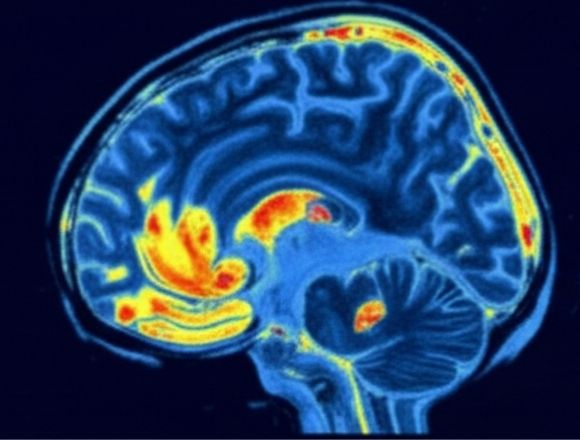

So ändert sich die Gehirnleistung nach 12 Wochen

Aufnahmen aus dem Testverlauf

*Basierend auf durchschnittlichen Ergebnissen von Studienteilnehmern